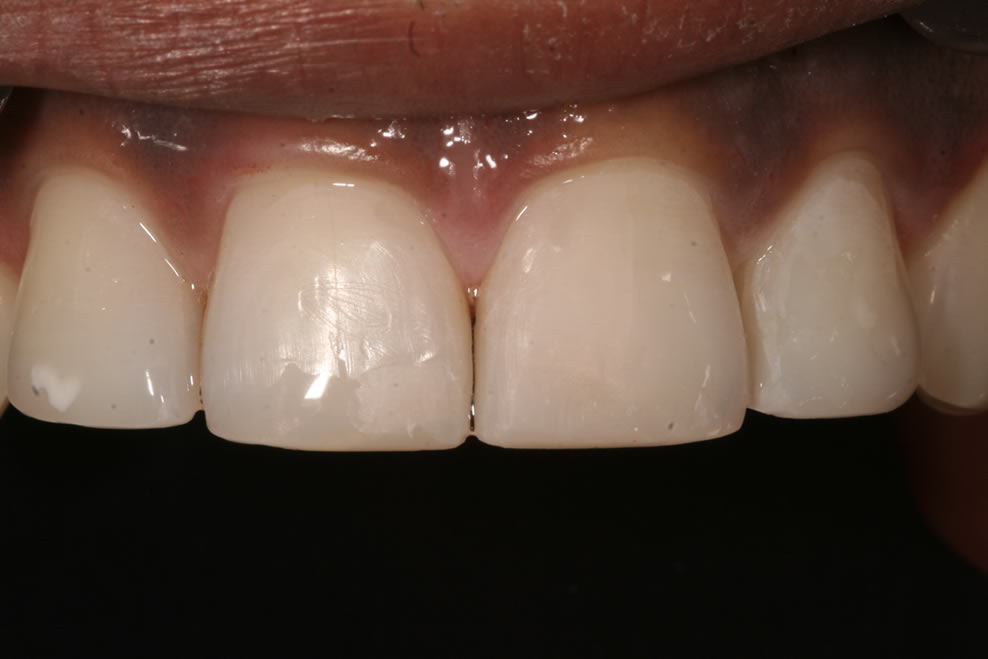

A white filling is a composite material made up of resin and glass, which is a tooth coloured and mercury free and can be used for many different purposes.

If you have a broken or decayed tooth, a composite filling can be used to restore the tooth to its original shape and colour.

Composite fillings can also be used for cosmetic purposes to restore chipped or uneven front teeth. Many patients also opt to have composite fillings used to replace old, unsightly silver fillings.